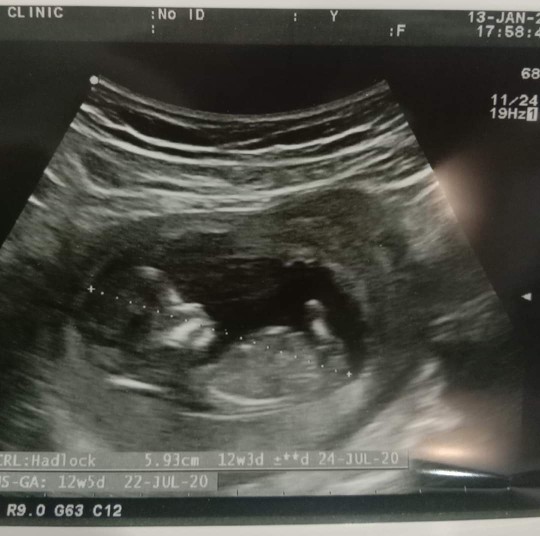

12W ค่ะ